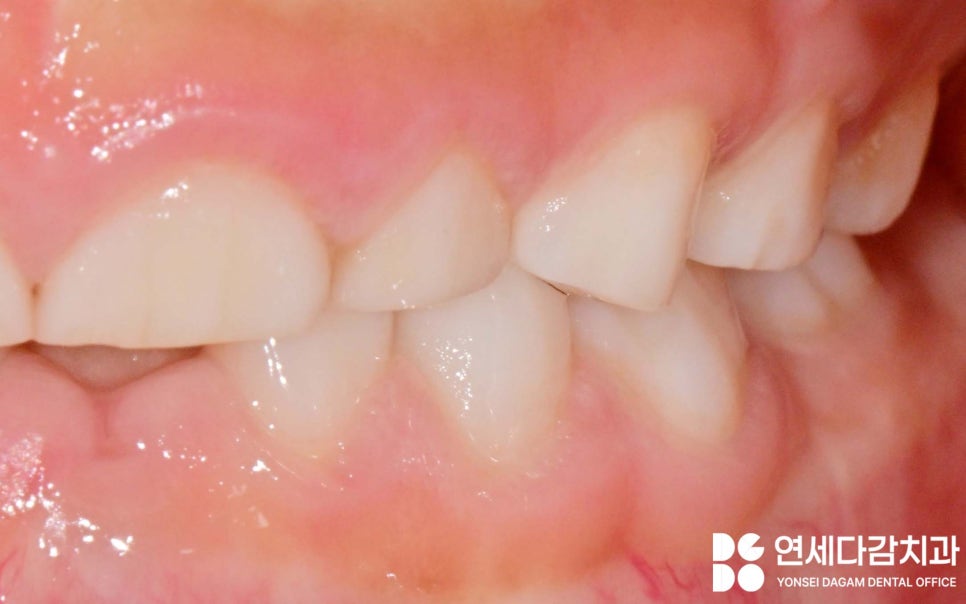

유치에서 영구치로 교체되는 시기에는

잇몸에서 새로운 치아가 자라면서

생기는 이질감에

무의식적으로 이를 갈 수도 있습니다.

턱 근육이 약한 아이와 달리

어른의 강한 턱 근육은 치아와 턱관절에

손상을 줄 수 있지만

소아는 그 절반 수준에 불과하여

턱관절에 미치는 영향이 제한적입니다.

마모된 유치는 결국엔 빠지기 때문에

영구치에 손상이 가는 문제를

걱정하지 않으셔도 됩니다.